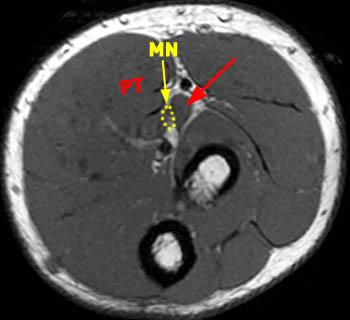

Your doctor has ordered a mri (magnetic resonance imaging) of your knee. Median Nerve Entrapment - Radsource

Median Nerve Entrapment - Radsource from radsource.us